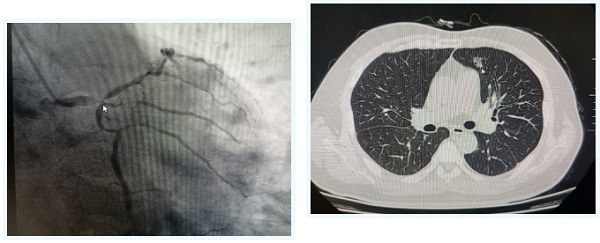

今年60岁的王先生数月前活动后突然出现心前区针刺样疼痛,持续时间不长就自行缓解了,便没有把疼痛当回事。但近期反复发作数次,遂到沧州市人民医院就诊。经初步问询,医生发现其有20余年的糖尿病病史,行冠脉造影检查后,揪出了引起王先生胸痛的病因:冠状动脉左主干重度狭窄99%,同时前降支回旋支重度狭窄,诊断为重度冠心病。

面对如此复杂的冠脉病变,心外科贺焱主任团队很快制定了冠脉搭桥的治疗方式。但在进一步完善术前检查的时候,胸部CT的检查结果显示王先生左肺上叶存在一个直径约1cm的毛玻璃结节。结节的影像特点具备了肿瘤的特征性影响表现:毛刺征、胸膜牵引、血管影。换句话说,王先生不仅患有重度冠心病,还可能患有肺癌。好在检查过程中并未发现远处器官转移和临近淋巴结肿大,也就是说,即便这个结节是恶性肿瘤,它的临床分期也属于早期,手术彻底切除几乎可以达到临床治愈的效果。